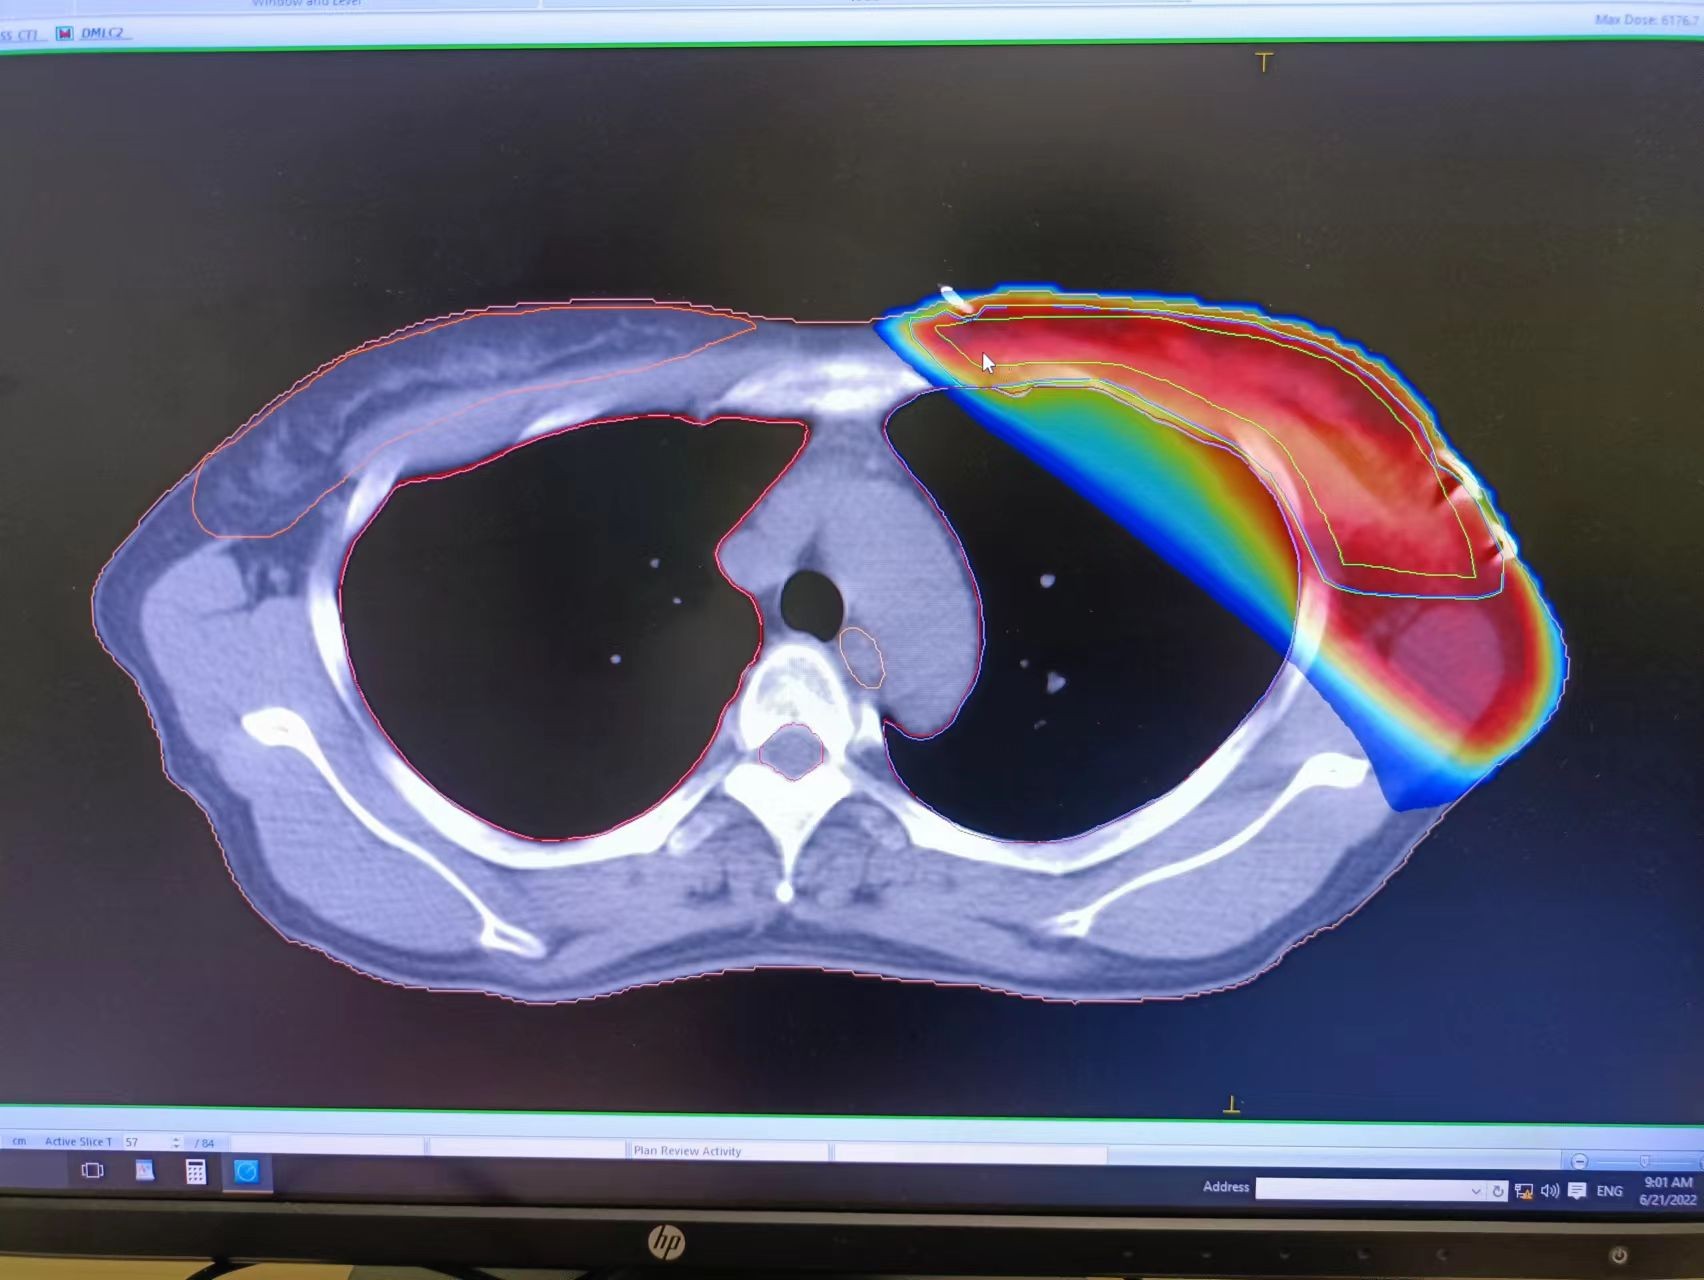

精准放疗是高能射线在3D图像引导下的精确放疗, 它通过CT定位,精准找到病灶,就像“巡航导弹”一样瞄准乳房本身、乳房切除术后的胸腔壁和(或)周围淋巴结,通过精准定位和精确的剂量计算,将放射治疗集中在病变靶区内,以高精度、高剂量、高疗效、低损伤以“清除”那些预谋在未来某天卷土重来的癌细胞;相比普通放疗或常规放疗,它对靶区内的放射剂量更高,周边的正常组织的损伤更小,不良反应更低。

经多方打听,沈小姐得知慈林医院的放疗设备是近两年从瑞典进口的医科达直线加速器,设备非常不错,医生也全是来自大三甲专科肿瘤医院,不但可以进行精准放疗,还可以根据病情选择三维适形放疗、调强放疗或是容积旋转调强放疗,于是最终决定来慈林肿瘤中心进行就诊放疗。

慈林医院放疗科的医科达Synergy直线加速器是世界上较先进的精确放疗设备,包含一台医科达Synergy直线加速器、Synergy XVI在线图像引导系统、IVIEWGT实时射野成像系统、MOSAIQ放射治疗系统、主动呼吸控制系统(ABC)、Monaco放射治疗计划系统和调强治疗计划验证系统。特别是其160片、厚度为5mm的多叶光栅(MLC),完全胜任常规放疗、普通三维适形放疗(3DCRT) 、容积调强、三维适形调强放疗(IMRT),更适合在3D、4D图像引导下的精确放疗(IGRT)等。 备注:因肿瘤病情复杂,可添加拔打0574-63995898或17788539772,咨询医师